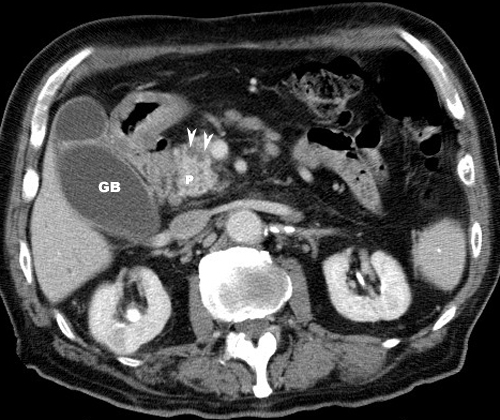

Pancreas Ct Scan Abdomen Cancer

Pancreas ct scan abdomen cancer. Your pancreas releases enzymes that aid digestion and produces hormones that help manage your blood sugar. This is usually the best initial test if you are worried about pancreatic cancer and is considered the single most useful imaging technique. Magnetic resonance imaging mri.

Ct scans of the pancreas can provide more detailed information about the pancreas than standard x rays of the abdomen thus providing more information related to injuries andor diseases of the pancreas. To help you prepare heres a look at what to expect. You might also have a ct scan of the chest to see if the cancer has spread into the lungs or lymph nodes there.

Since a ct scan visualizes all of the abdominal organs it is also very useful in detecting any spread of the cancer to the liver or nearby lymph nodes. A ct scan for pancreatic cancer uses x ray images to present detailed images of the pancreas. A ct scan helps doctors make a pancreatic cancer diagnosis.

Why you might have it. Using magnetic waves a scanner creates detailed images of the abdomen in particular the area around. Ct scans of the pancreas are useful in the diagnosis cancer of the pancreas and pancreatitis.

Well explain why your doctor may. You might have this test to find out if you have pancreatic cancer or to see how big it is and whether it has spread. In short a ct computerized tomography scan can show the pancreas pretty clearly and is a trusted modality when pancreatic cancer is suspected.